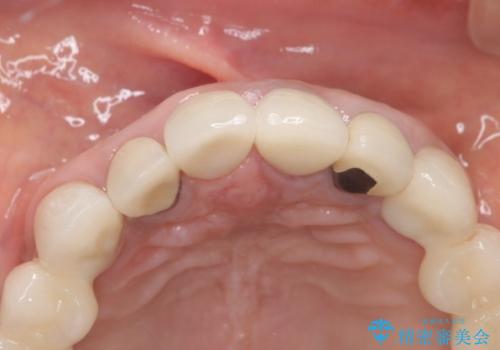

オールセラミッククラウンにすることで、色と形態をきれいにすることができました。